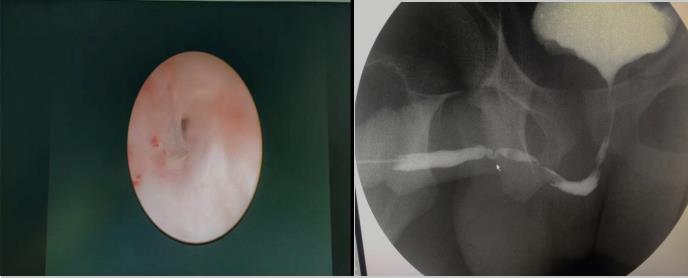

内蒙古17岁的高三学生小马,10年前做阑尾切除手术,术后因留置尿管,逐步出现排尿不畅,从站立时排尿滴沥,尿线细,到站立时无法自解小便,后逐渐养成蹲位排尿习惯。正值高三关键阶段的小马,自觉排尿不畅较前明显加重,已严重干扰平日学习和生活,痛苦不堪。父母带小马先后在内蒙、上海等地就诊,后经亲戚介绍,在我院泌尿外科入住。入院后强永春主任了解其病情后,通过尿流率检测、尿道镜检查及尿道造影,明确患者前尿道两段狭窄。与家属充分沟通后,泌尿外科团队精心术前准备,在全麻下行“颊粘膜尿道成形术”,术中证实前尿道两处狭窄,狭窄段长8㎝,取两侧颊粘膜各4×1cm,重建修复尿道狭窄。术后第2天,患者可进少量流食,说话正常,术后1周患者带管好转出院,出院3周患者来院复查,主管医师张顺给予拔除尿管后,小马终于露出久违的笑容:“终于可以站着排尿了”。术后站立位查自然尿流率示:最大尿流率 19.2ml/s。手术效果满意。

强永春副主任介绍说:尿道狭窄最常见的症状是尿流减少和膀胱不完全排空,也可以表现排尿困难、尿路感染、附睾炎、残余尿量多。该患者考虑为尿路感染所致。尿道狭窄以往采用尿道扩张、内镜切开及尿道成形术治疗,但长段的狭窄手术后效果并不满意,现在有了粘膜组织移植,组织移植常选择口腔粘膜(颊粘膜、舌粘膜和唇粘膜),手术效果好,但手术要求高,难度大。